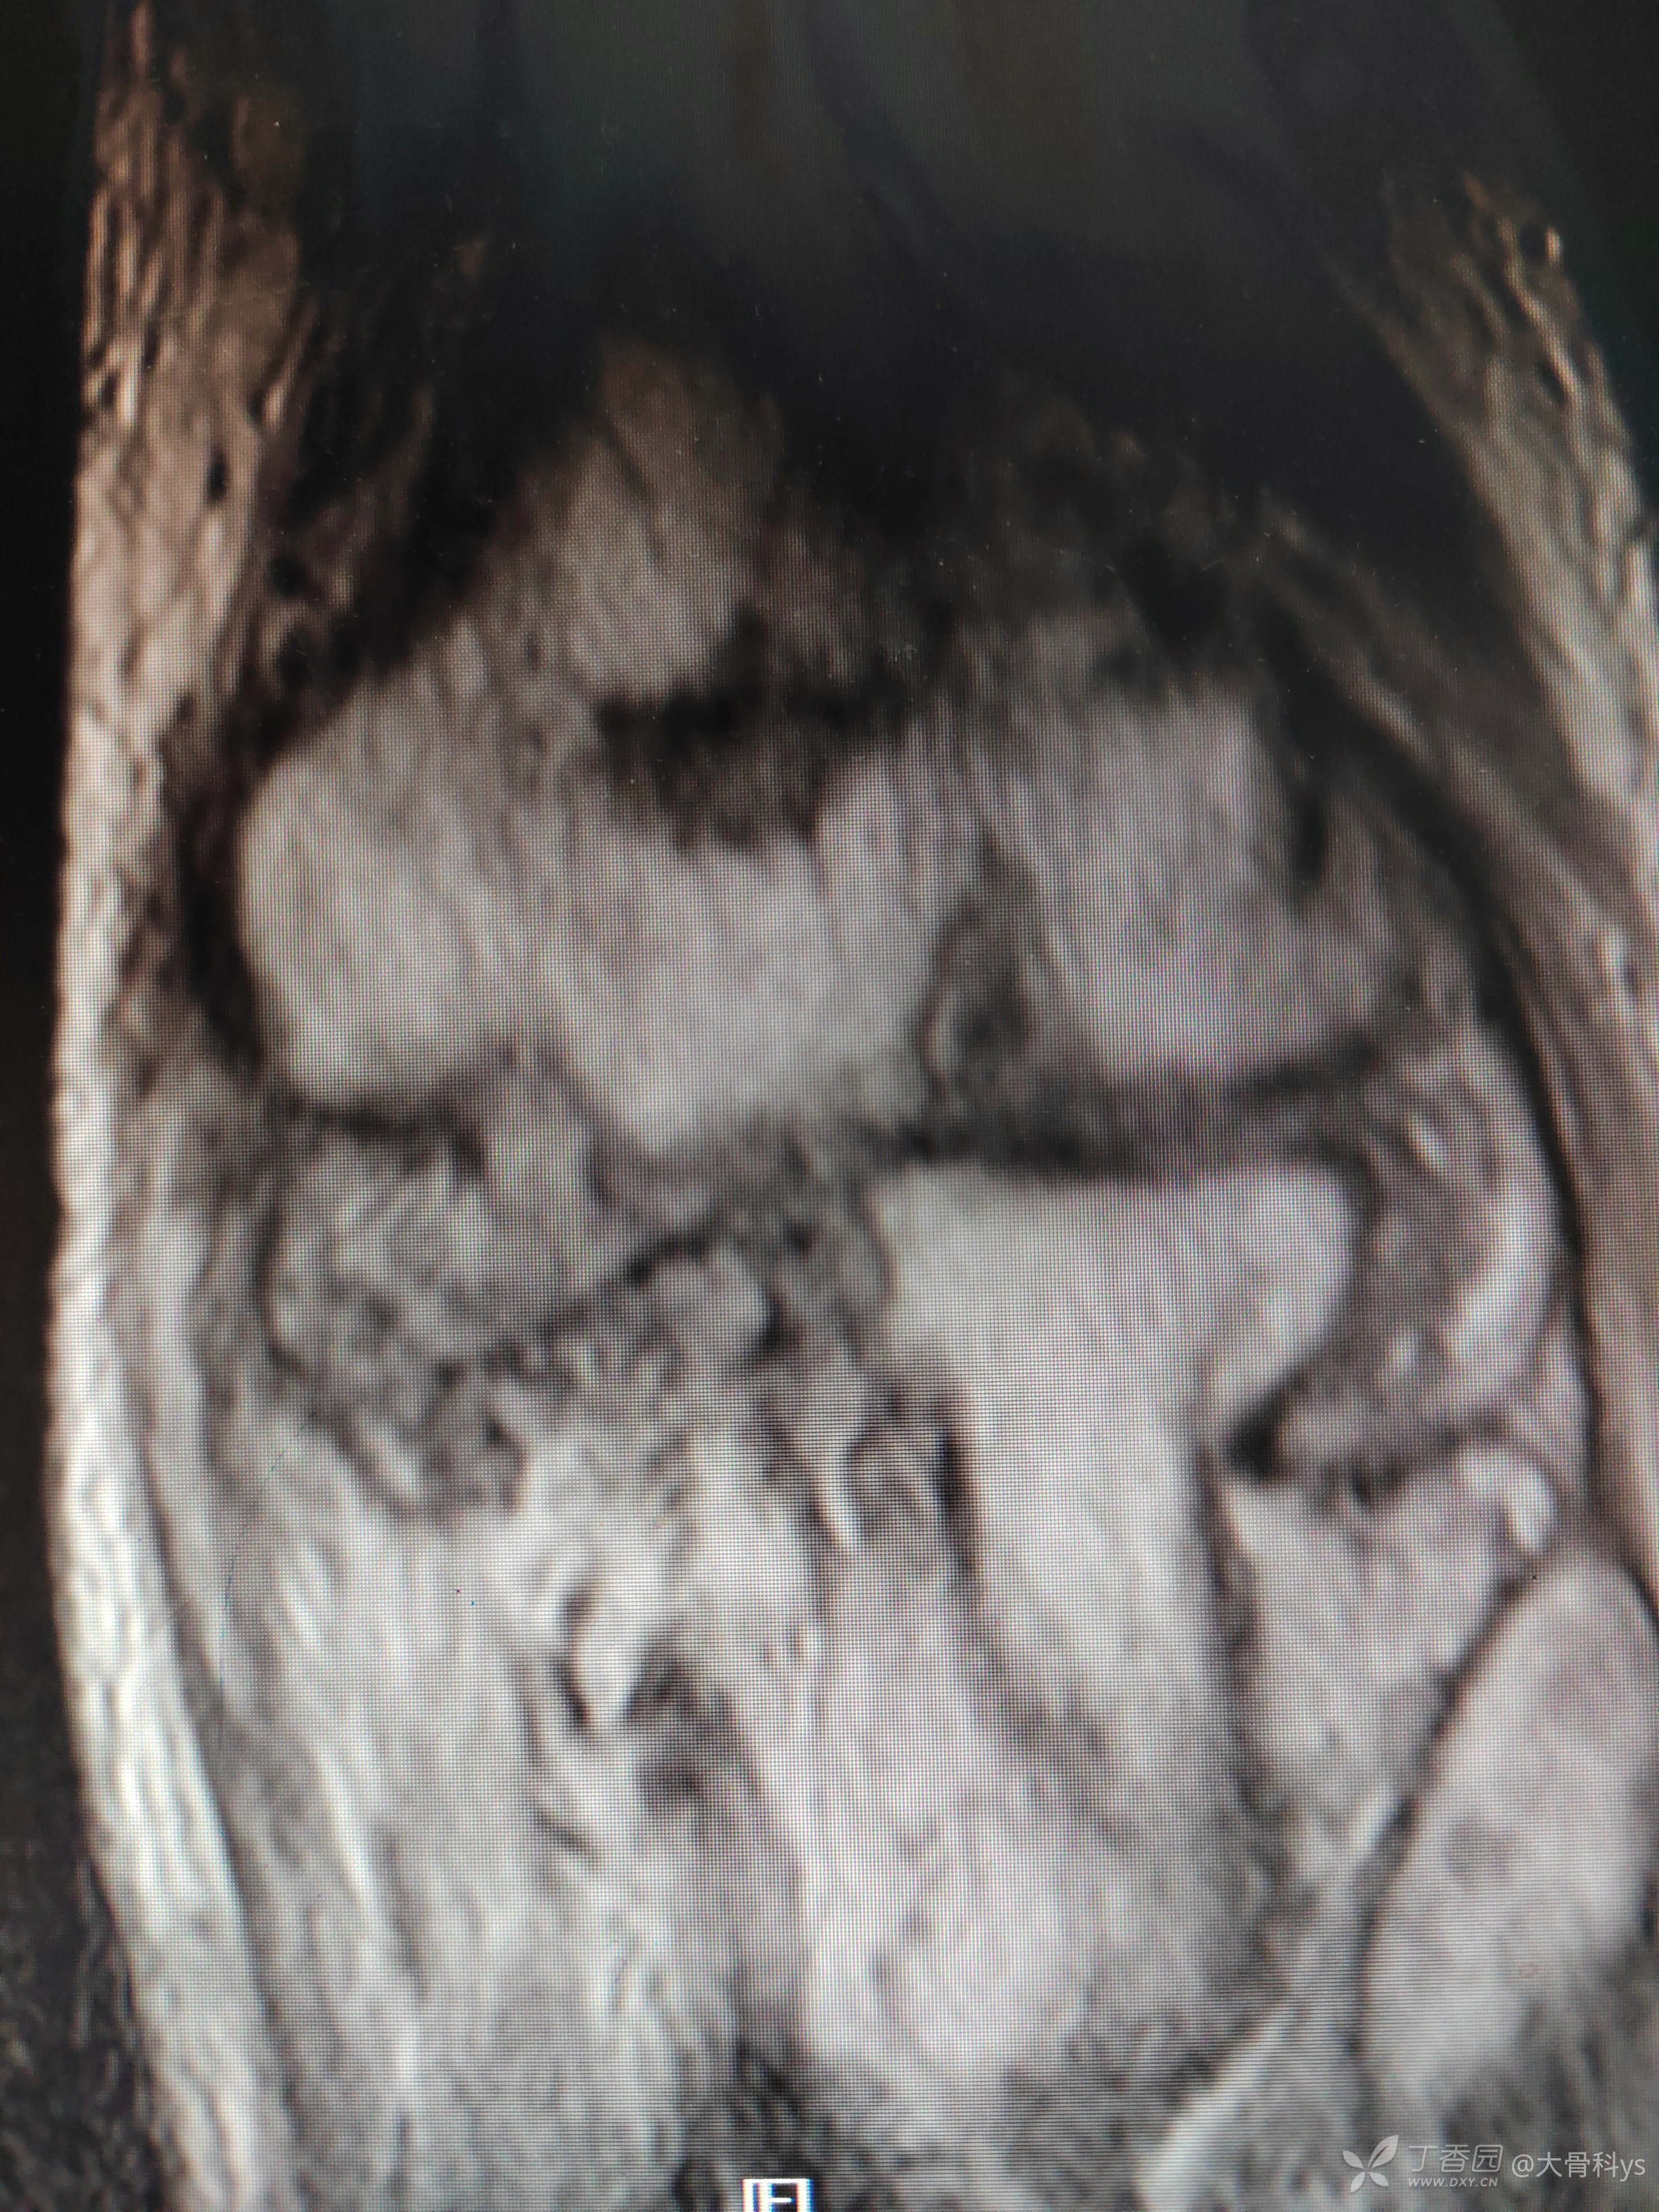

影像学资料

考虑肘关节结核,行关节腔清理+骨髓炎病灶清除+负压封闭引流术。病灶组织再次培养,病灶组织结核杆菌培养,找抗酸杆菌,结核杆菌核酸及利福平耐药检测结果暂未回报。